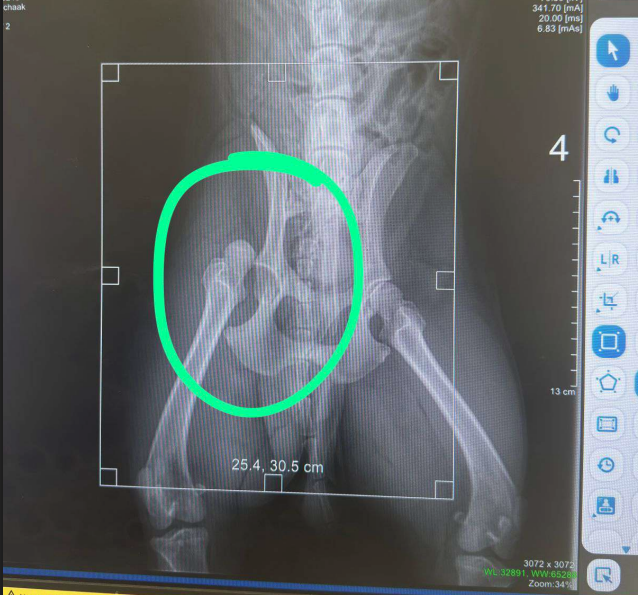

Conforme Ciro Souza, após o acidente Mochak foi levado a uma clínica, onde foi constatada uma luxação grave no quadril. O animal precisou ser medicado, submetido a exames de sangue e eletrocardiograma, e, conforme raio-x que confirmou a suspeita, foi encaminhado para cirurgia de emergência. Ele passou a noite internado e recebeu alta no dia seguinte, para recuperação em casa.

Os gastos iniciais, apresentados pelo tutor, totalizaram R$ 4.280,77, incluindo R$ 462,00 para raio-x, eletro e exame de sangue; R$ 48,80 para medicamentos comprados no dia do acidente; R$ 3.400,00 para cirurgia, anestesia e internação; R$ 254,87 para medicamentos adquiridos no dia da alta; e R$ 118,00 para gabapentina, um medicamento formulado.